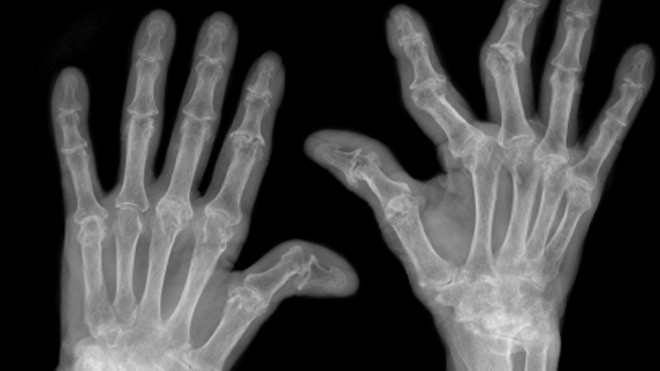

Có những điểm tương đồng trong chẩn đoán, chụp Xquang của một khớp bị ảnh hưởng có thể phát hiện một trong hai bệnh vừa nêu. Có thể chọc hút dịch khớp để phân tích thành phần. Kết quả của các xét nghiệm này giúp phân biệt giữa viêm xương khớp với viêm khớp dạng thấp.

Hình ảnh của viêm xương khớp (bên trái) và viêm khớp dạng thấp (bên phải)